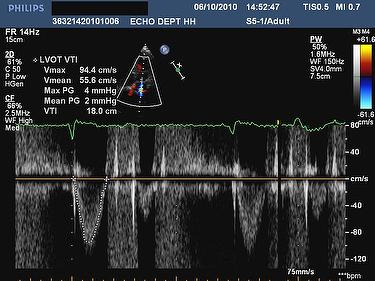

Aortic stenosis with its abrupt widening from the small orifice to the larger aorta has an unfavorable geometry for pressure recovery. Vmax across the Aortic valve is > 4m/s. 2. Calculated aortic valve area of 1.34 cm2. 3. LVOT Vmx / AV Vmx ratio < 0.25. 4. ... Visit Document

Low Flow Low Gradient Aortic Stenosis With Preserved LVEF

Calcified aortic valve LVOT VTI 11 cm LVOT 19.5 mm SVI 23 ml/m² Low cardiac output Vmax = 3.5 m/s Mean Gradient 30 mmHg AVA 0.42 cm² , AVAi 0.29 cm²/m² Severe AS, Low Gradient LVEF = 68%, LVH . Normal LVEF Patient 1: recent pulmonary edema . ... View Full Source